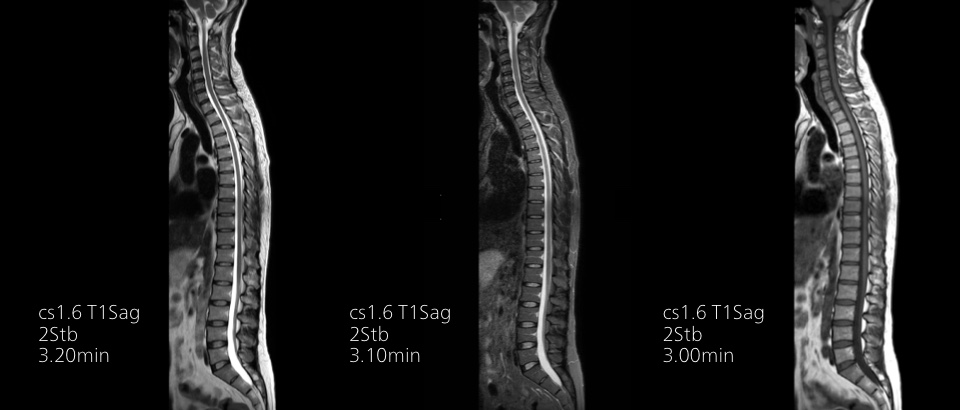

Turn images into answers – 50% faster

Put time on your side with Compressed SENSE to reduce scan time up to 50%2 with virtually equal image quality. Create exceptional MR images with 60% higher resolution for confident diagnosis.

16:30 minutes

Conventional

8:00 minutes

Compressed SENSE